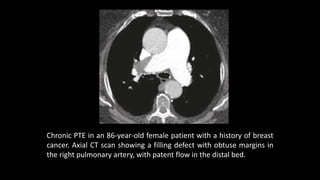

Chronic PTE in an 86-year-old female patient with a history of breast

cancer. Axial CT scan showing a filling defect with obtuse margins in

Chronic PTE inan 86-year-old female patient with a history of breast cancer. Axial CT scan showing a filling defect with obtuse margins in the right pulmonary artery, with patent flow in the distal bed.